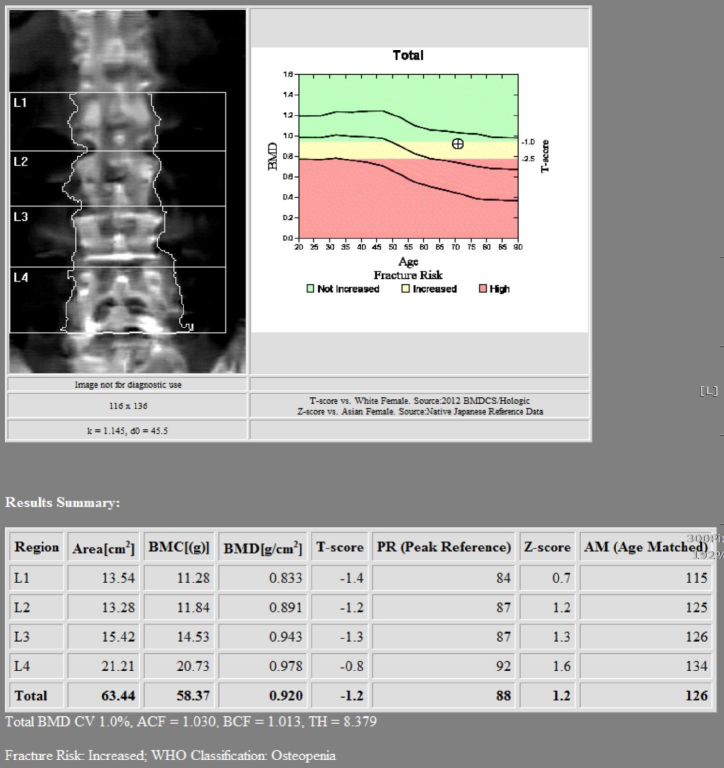

骨質密度攝影檢查可以測量您的骨質密度,將您的骨質密度與已經確立的骨質密度

平均值或標準值進行比較,可以計算出一個比較值;本院新進HOLOGIC的骨質密度測量

儀可測量髖關節、腰椎及全身骨骼密度,可用於骨骼骨質密度評估和骨折風險評估;檢查

骨質密度的量度標準是T評分 (T-score),用來介定是否患上骨質疏鬆症。方法是將雙

能量X光吸收儀得出的T-分,把骨質疏鬆程度分類的骨質密度與處於骨質密度高峰期的同種

族年青人作出比較,以顯示骨質流失的

程度。

以下是根據世界衞生組織的標準,用雙能量X光吸收測量儀得出的T-分把骨質疏鬆程度分類:

世界衛生組織根據骨質密度水平對於骨質疏鬆症的分級方式

骨質密度檢測結果(T評分)

高過-1

-1至-2.5

低於-2.5